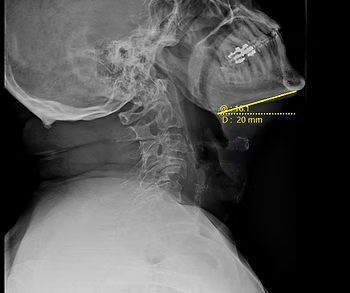

Motion X-Rays: Looking Up & Range of Motion

This is a view of a person's neck from the side and they're looking up. When this patient first started care, they could only look up at about 16 degrees. After completing an initial care plan, they are now able to look up at about 35 degrees, which is close to normal. At the end of the day, this person wasn't able to look up and the quality of life of that person was greatly diminished, in addition to the function of the body. The range of motion in the neck in this person was greatly increased. This can lead to fewer headaches, less tension, and more mobility in the cervical spine. A person who sees improvement in this area would have fewer blind spots while driving and better overall posture.

Cervical X-Ray Prior to Chiropractic Care: Patient standing normally, looking up as high as they are able